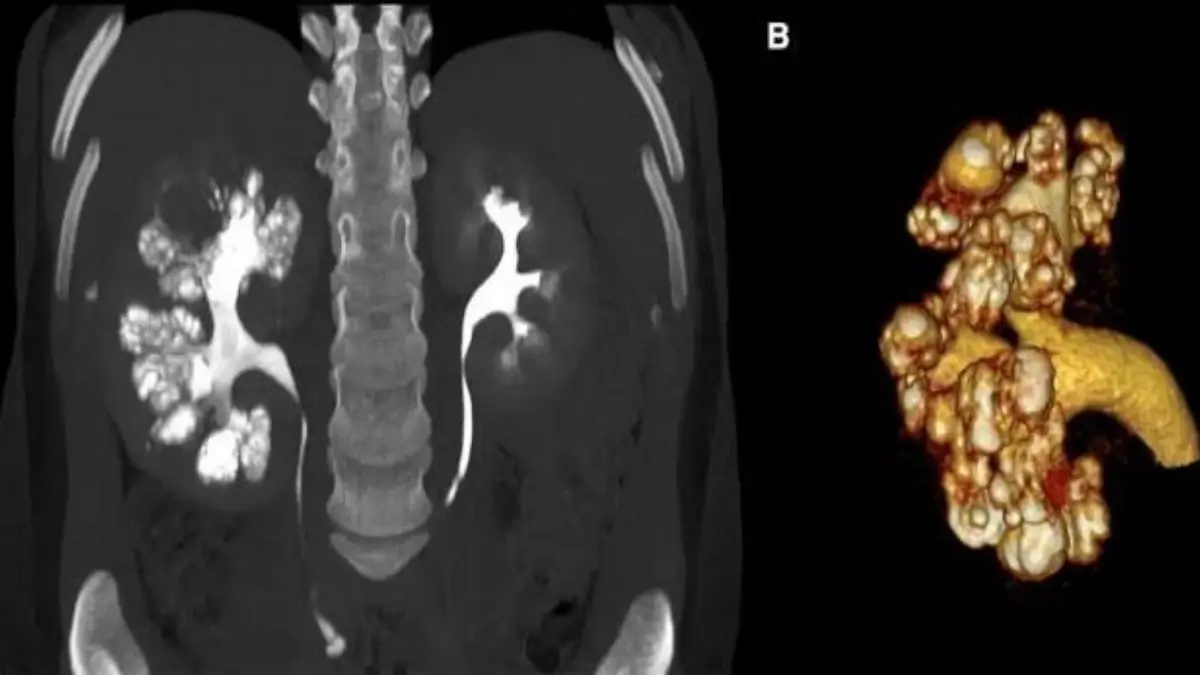

কিডনির দু’টি অংশ থাকে। একটিকে বলে কর্টেক্স এবং অপরটি মেডুলা। কিডনির মেডুলা অংশে কোনো কারণে সিস্ট তৈরি হলে তা দেখতে অনেকটা স্পঞ্জের মতো লাগে এবং এই কারণে এটিকে মেডুলারি স্পঞ্জ কিডনি বলে।

Medullary Sponge Kidney নির্ণয়ের জন্য ভালোভাবে রোগীর ইতিহাস জানতে হবে। পরিবারের কারোর এই রোগ আছে কি না তা প্রথমেই ভালোভাবে জেনে নেওয়া উচিত। তবে সঠিকভাবে রোগ নির্ণয়ের জন্য রোগীর ইতিহাস জানার পাশাপাশি প্রয়োজনীয় পরীক্ষা নীরিক্ষার কোনো বিকল্প নেই। যেসব পরীক্ষার মাধ্যমে রোগটি সনাক্ত করা সম্ভব হয় সেগুলো হলো আইভিইউ, আল্ট্রাসনোগ্রাম, সিটিস্ক্যান, ইত্যাদি।